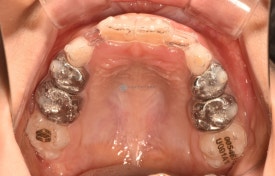

투명교정 10개월차입니다.

치료 후 - 유치 어금니들이 빠지고 영구치가 맹출하고 있습니다.송곳니가 나올 공간을 충분히 마련하며 확장하여 고른치열을 완성했습니다.

이대로 끝내도 좋겠지만 어린이투명교정치료의 18개월 기간이 아직 만료되지 않았습니다. 영구치 어금니 맹출을 조금 더 기다리다가 송곳니 어금니들이 맹출되면 그때 다시한번 장치를 만들어 앞니 디테일 마무리와 함께 새로 맹출하는 이들을 완벽하게 하고 마무리해하면 2차교정이 필요없을 것으로 생각됩니다.